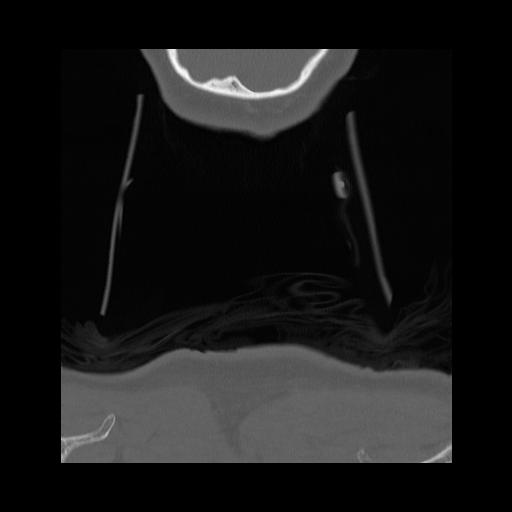

16 HUESO,,Coronal,2.000,HUESO,Coronal,